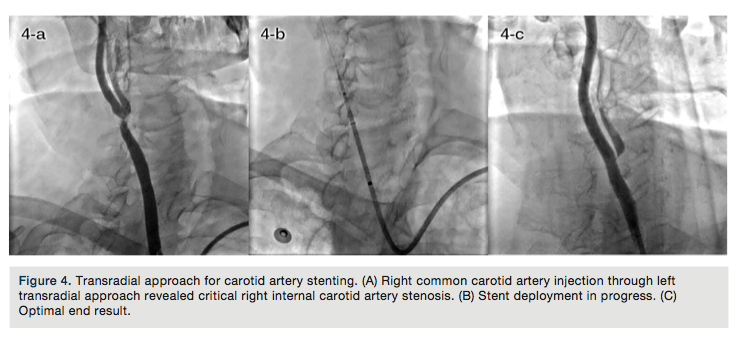

TRA for renal artery stenting. Renal artery stenting techniques have evolved over time, shifting from the use of larger 8 French (Fr) sheaths or guide catheters required to allow the passage of a bulky stent system over .035-inch wires to contemporary 6Fr compatible devices over .014-inch PTCA wires.12,20-22,44 This evolution in hardware actually increased the safety and efficacy of renal artery stenting, leading to its performance in coronary-like fashion and the evolution of TRA as an effective alternative approach for TFA.

The renal artery most commonly points downward after its origin; thus, TRA offers more co-axial and less traumatic guide catheter cannulation as compared with TFA (Figure 1A).

Renal artery diameter usually ranges from 4 to 7mm; 6Fr (or at most, 7Fr) guide-catheter compatible balloons and stents can comfortably be used via TRA (Figures 1B and 1C).